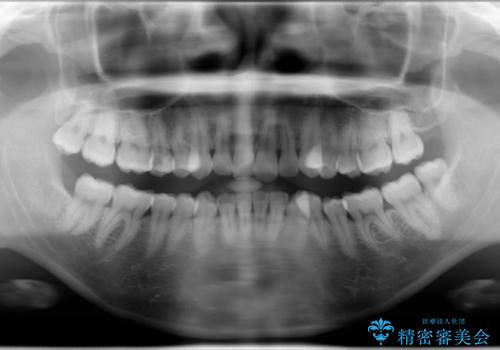

- 上顎両側第1小臼歯、下顎左側第2小臼歯の3本を抜歯、ラビアルのワイヤー矯正を計画した。

抜歯矯正は抜歯にできたスペースをつかい、前歯を積極的に下げたり、大きなガタつきを取り除くことができますが、その分時間がかかります。

ワイヤーを用いることで、矯正中に生じる様々な問題にその場で対処することができます。